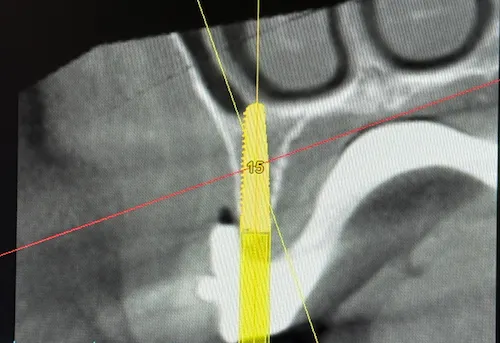

Unter Einsatz der SIMPLANT® Planungssoftware kann der Implantolgoe die optimalen Implantatpositionen vorab am Computer planen, wobei sämtliche Planungsdaten anschließend in die Herstellung einer individuellen Bohrschablone einfließen. Die Bohrschablone ermöglicht ein punktgenaues, schonendes Einsetzen der Implantate an den zuvor geplanten Positionen, minimiert das Verletzungsrisiko und beschleunigt letztendlich die Heilung.

Das Behandlung mit Camfour™ sieht 4-6 Implantate je Zahnbogen vor. Meist reichen jedoch 4 Implantate aus. Die speziell für diesen Zweck ausgelegten Zahnimplantate werden mit einem Winkel von bis zu 45° in den Knochen eingebracht. Durch die geneigten Implantate ist der Spezialist für Implantologie unabhängiger vom noch vorhandenen Knochenvolumen und kann ohne einen vorherigen Knochenaufbau implantieren. Wichtig ist, dass die Zahnimplantate bereit unmittelbar nach Einsetzen stabil im Kieferknochen sitzen. Dies wird durch das spezielle All-on-4 ® / All-on-6 ®- Implantationsverfahren sichergestellt. Eine hohe „Primärstabilität“ der Implantate ist die wichtigste Grundvoraussetzung für eine Sofortversorgung mit Zahnersatz noch am gleichen Tag.

Bevor an einen operativen Eingriff gedacht werden kann, stehen als erstes Röntgenbilder mithilfe der Digitalen Volumentomographie auf dem Programm. Hier sind die Überreste in Ober-und Unterkiefer gut zu sehen, vor allem aber die Positionen der abgebrochenen Zahnwurzeln. Auf Basis der Bilder können die Positionen für die insgesamt 8 Implantate auf den Millimeter genau geplant werden: Unser Patient wird jeweils 4 Implantate im Ober-und Unterkiefer erhalten, die im Nachgang jeweils mit einem festsitzenden Zahnersatz versorgt werden. Die Einheilphase dauert zwischen 4 und 6 Monate, prognostiziert Dr. Mintert, der Spezialist für Implantate in der ZPK Herne.